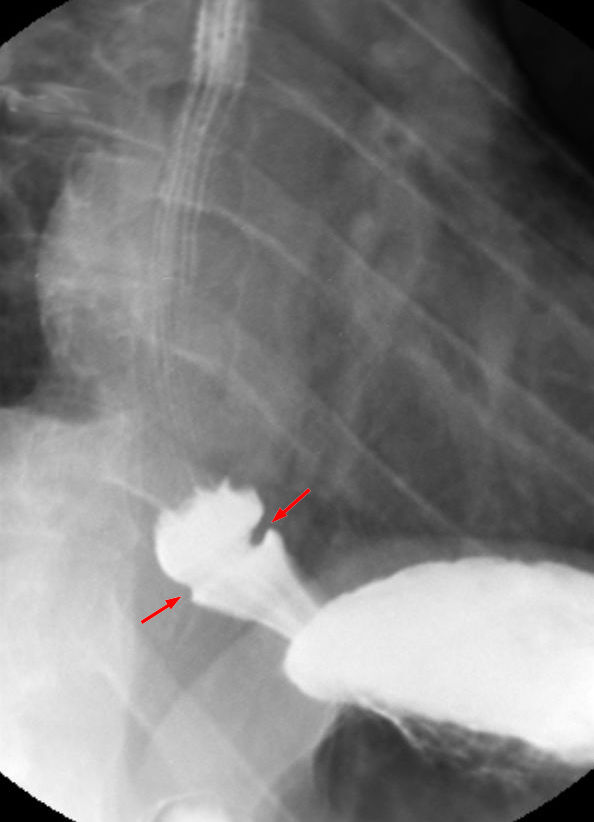

샤츠키고리는 보통 식도위십이지장 내시경 검사 또는 바륨 연하 검사로 진단한다. 내시경 검사에서는 식도의 내강 내에 다양한 크기의 링이 나타나는데, 이는 일반적으로 식도가 위와 연결되는 위식도 접합부에서 몇 센티미터 위에 위치한다. 샤츠키고리는 식도 웹과 유사하게 보일 수 있으나, 식도 웹은 추가적인 점막 조직을 포함하지만 식도를 완전히 둘러싸지는 않는다는 차이점이 있다.

4. 2. 바륨 삼킴 검사

샤츠키고리는 보통 식도위십이지장 내시경 검사 또는 바륨 연하 검사로 진단한다. 내시경 검사에서는 일반적으로 식도의 내강 내에 다양한 크기의 링이 나타난다. 이 링은 일반적으로 식도가 위와 연결되는 위식도 접합부에서 몇 센티미터 위에 위치한다. 샤츠키고리는 종종 식도 웹이라는 관련 질환과 유사하게 보일 수 있다. 식도 웹 역시 추가적인 점막 조직을 포함하지만 식도를 완전히 둘러싸지는 않는다.

다른 이유로 시행된 내시경 검사 및 바륨 연하 검사에서 종종 예상치 못한 샤츠키고리가 발견되기도 하는데,[7] 이는 많은 샤츠키고리가 증상이 없음을 의미한다.